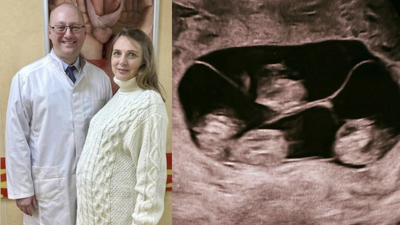

Woman in Russia gives birth to four identical girls/Image: RT

A rare and medically significant birth has been reported in St Petersburg, where a woman delivered four identical baby girls, marking the first such case officially recorded in Russia.The delivery, which took place at a maternity hospital in the city, has drawn attention due to its extreme rarity. Medical estimates suggest that monochorionic, or identical, quadruplets occur in around one in 15.5 million births. Globally, only about 15 such cases have been documented.All four babies were born at 32 weeks of pregnancy and are reported to be in stable condition. Their birth weights ranged between 1,360g and 1,640g, and their lengths were between 37cm and 41cm.

Doctors described these figures as strong for babies born at this stage.In a statement shared by the hospital on Russia’s social media platform VKontakte, the team said, “Four charming sisters were born at 32 weeks. According to estimates, monochorionic (identical) quadruplets occur once in 15.5 million births. Such unique births have not been reported in the country.”What makes the case particularly complex is that all four babies developed from a single fertilised egg and shared one placenta, a condition known as a monochorionic pregnancy.